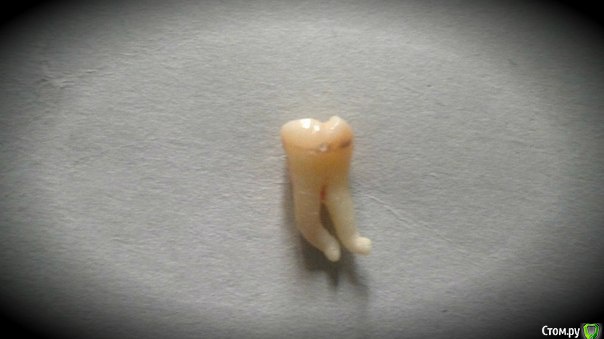

Alejandro Опубликовано 4 ноября, 2015 Поделиться Опубликовано 4 ноября, 2015 (изменено) http://s019.radikal.ru/i601/1511/3a/9ef44aebe128.jpghttp://s019.radikal.ru/i626/1511/11/6c08142f1f77.jpgТакой вот свежеиспечённый 28 ) Изменено 4 ноября, 2015 пользователем Alejandro 5 Ссылка на комментарий